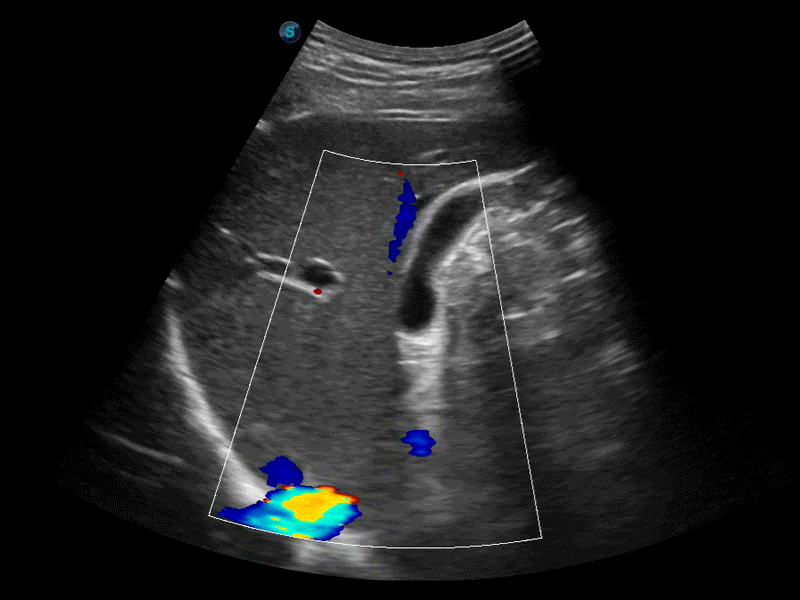

• 扩展成像技术

凸阵、线阵和相控阵探头进行实时扫描时,开启扩展成像模式,可以扩展超声图像视野,以便更完整地查看大的病灶或组织器官的解剖结构。